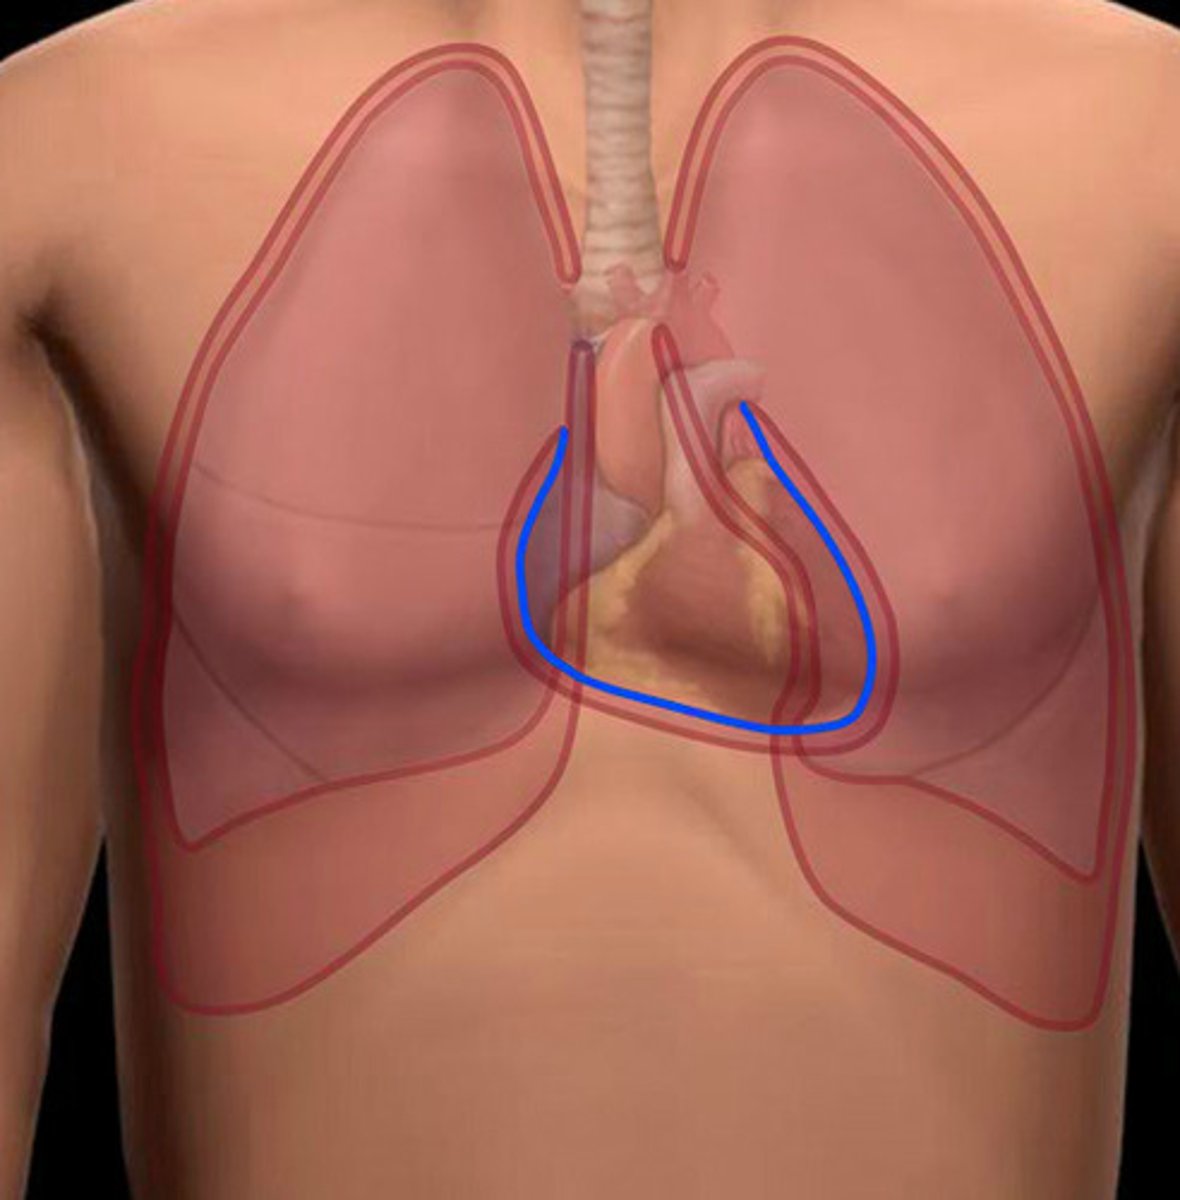

superior vena cava, right atrium, tricuspid valve, right ventricle, pulmonary valve, L+R pulmonary artery, lungs, L+R pulmonary veins, left atrium, mitral valve, left ventricle, aortic valve, aorta, rest of the body

circulation of blood through the heart